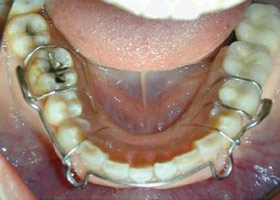

4. 使用活動式矯正裝置矯正中(矯正方式因人而異)。